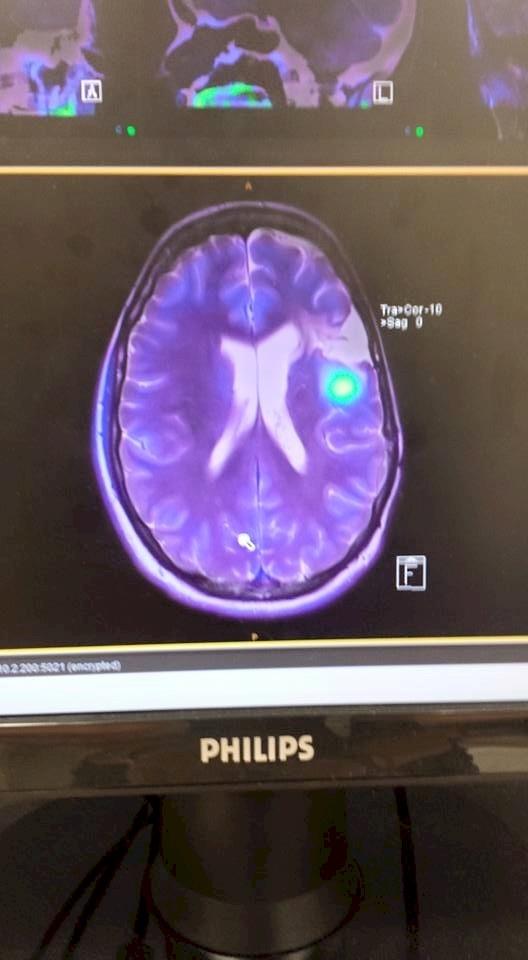

• PET scan - my radioactive brain.

The bright blue dot in this scan is obviously the tumour and the white patch above it is where the previous tumor was removed.

The new tumor looks quite big but apparently it's only around 5 mm.

Here's hoping its no longer there or at least a whole lot smaller when it comes time for the next scan!